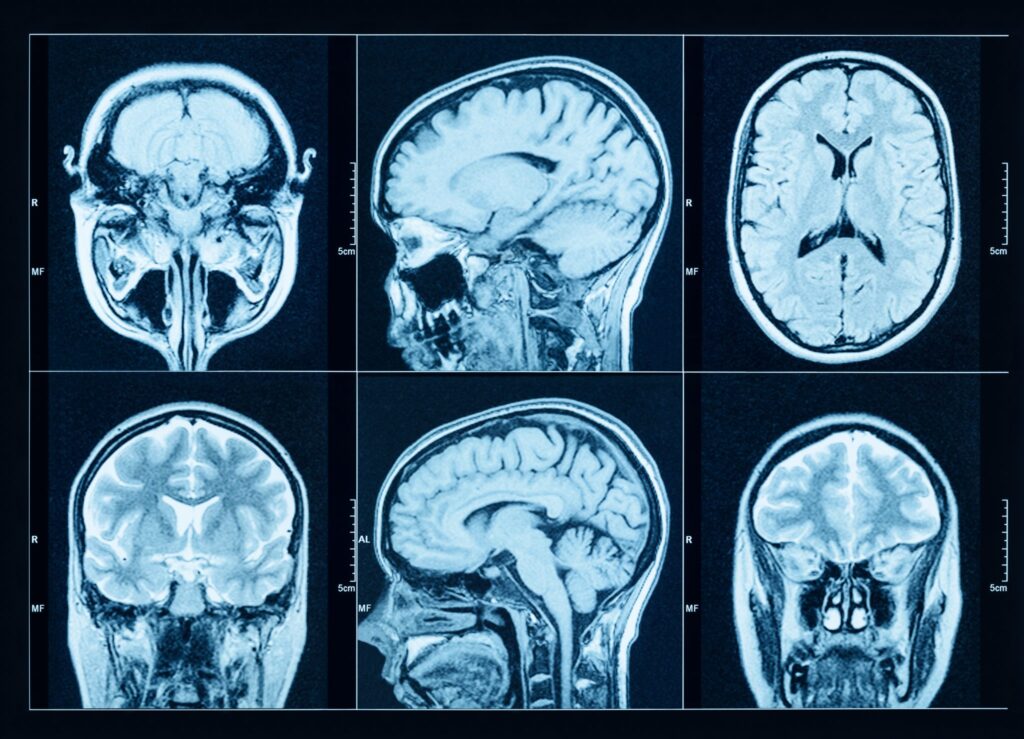

The Ishibashi Research Laboratory at Boston University specifically focuses on understanding how CHD and subsequent cardiac surgery impact the rapidly developing brain during the fetal, neonatal, and infant stages. We utilize cutting-edge neuroscience techniques in a variety of clinically relevant experimental models to study and research mechanisms of brain injury and immaturity.

Many children with congenital heart disease (CHD), especially those with the most complex conditions, experience behavioral challenges and neurodevelopmental delays even after successful surgical correction.

The long-term goal of our research program is to optimize treatment strategies and develop novel therapies that reduce neurodevelopmental impairment in children living with CHD.